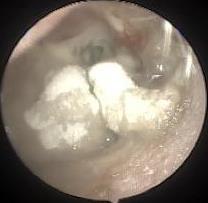

• 耳内镜下耳屏软骨-软骨膜鼓膜修补术后的短期疗效观察

摘要:目的 探讨耳内镜下耳屏软骨-软骨膜鼓膜修补术后的短期疗效。方法 回顾性分析2019年9月-2022年8月该院收治的78例鼓膜穿孔患者的临床资料,患者均采用耳内镜下鼓膜修补术。术后随访3个月,观察鼓膜形态和穿孔愈合情况,记录内镜图像、干耳时间、术前术后听力及耳鸣情况,以及外耳道狭窄等并发症的发生率。结果 术后3个月,鼓膜穿孔愈合率为97.44%(76/78),愈合良好,平均气导听阈较术前明显改善,气骨导间距较术前明显缩小,耳鸣较术前明显改善,差异均有统计学意义(P<0.05)。干耳时间为(4.21±1.12)周。术后出现肉芽5例,再穿孔2例,真菌感染2例,术腔感染、耳屏感染、外耳道狭窄和切口瘢痕各1例,所有患者术后均未发生面神经麻痹和感音神经性聋等严重并发症。结论 耳内镜下耳屏软骨-软骨膜鼓膜修补术是一种安全、有效的手术方法。根据术后愈合规律、内镜下鼓膜和外耳道形态特征,可为鼓膜修补术后正常中耳转归和并发症的诊疗,提供临床参考。